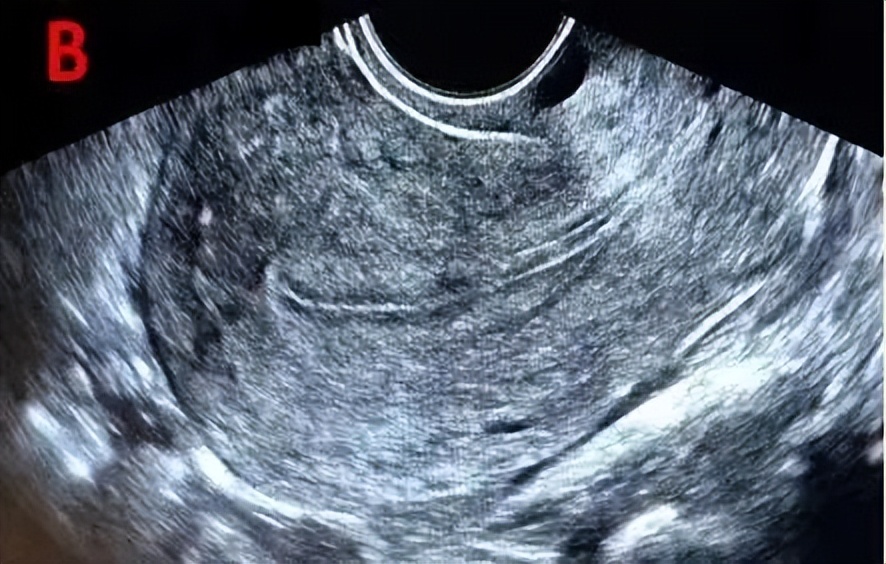

B型为弱三线型,为均一的中等强回声,宫腔中线回声不明显,一般见于黄体早期。

C型为均质强回声,为均质强回声,无宫腔中线回声,一般见于黄体晚期。